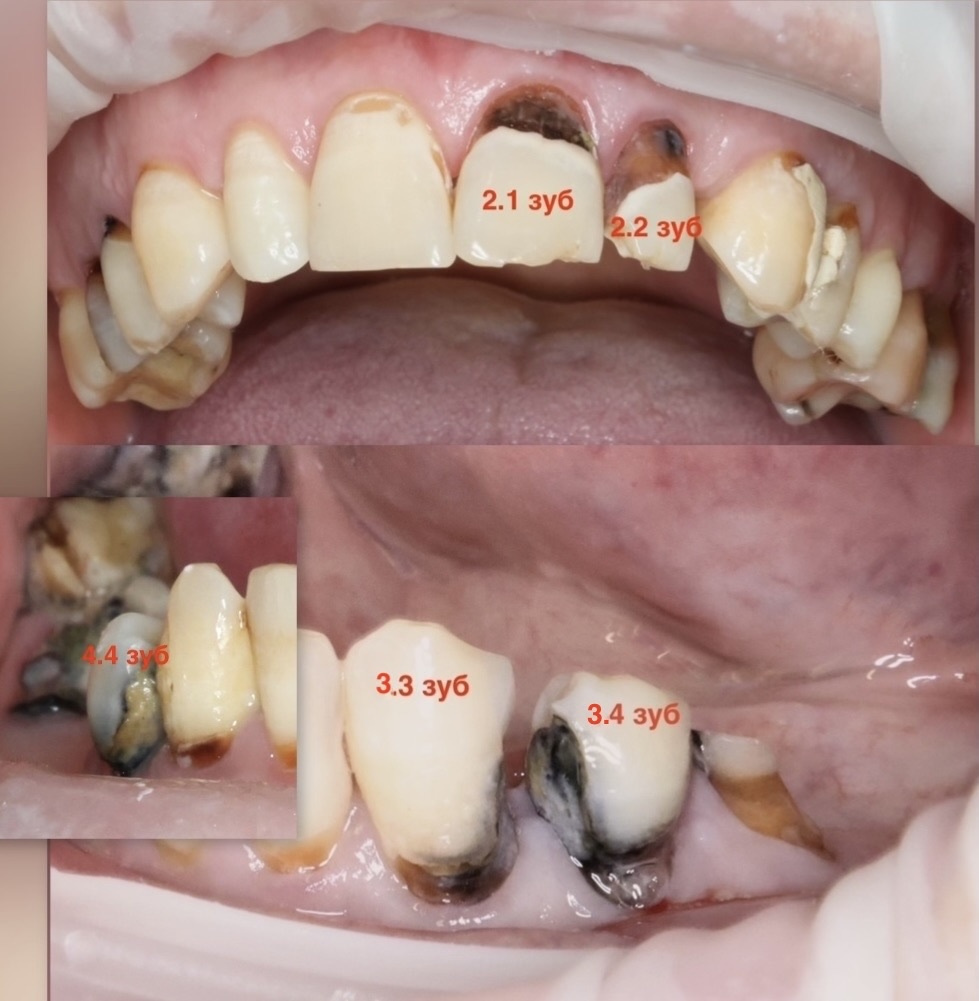

Прошло почти два года и на контроль пришёл пациент, в успех лечения которого могли не верить многие. Чёрные зубы с глубокими поражениями даже на корнях, работа без микроскопа, при обработке полостей пульпа аж просвечивалась, но жизнеспособность её удалось сохранить во всех 5 зубах, за которые взялся терапевт. Удалось обойтись без депульпирования. Статья от 9 февраля 2024 года: Для многих это звучит как фантастика, ведь привычный сценарий - удалить нерв, чтобы не рисковать. А то мало ли что. Сегодня, спустя 1 год и 8 месяцев, готова показать отдалённый результат. Все ли зубы выжили? Как выглядят пломбы? Какие прогнозы на дальнейшую жизнь? Вспомним старую компьютерную томограмму, ещё до лечения сделанную, самые экстремальные полости оценим: Меньше миллиметра тканей отделяет кариозные полости от нерва. При таких глубоких поражениях многие депульпировали бы зубы "для надёжности". И пациенты, часто, того же мнения придерживаются - надёжнее удалить нерв. Собственно, так и есть. Но есть врач

Прошло почти два года и на контроль пришёл пациент, в успех лечения которого могли не верить многие. Чёрные зубы с глубокими поражениями даже на корнях, работа без микроскопа, при обработке полостей пульпа аж просвечивалась, но жизнеспособность её удалось сохранить во всех 5 зубах, за которые взялся терапевт. Удалось обойтись без депульпирования.

Вот и в данном случае, по прошествии 1 года и 8 месяцев, можно с уверенностью утверждать, что всё прошло успешно. Оценим свежие срезы (ноябрь 2025 года) КЛКТ, а сверху в коллаж я добавила фотографии полостей, которые были очищены от кариеса в феврале 2024 года (для оценки серьёзности ситуации):